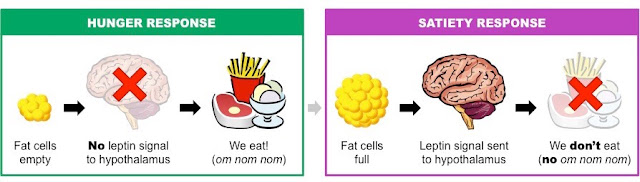

درس الباحثون أيضًا تأثير هرمونات اللبتين leptin والغريلين ghrelin في طريقة أكلنا. يُعتقد أن كلًا من اللبتين والغريلين ينظمان السلوك من خلال تأثيرهما في جهاز الدوبامين الحوفي، وهو مكوِّن رئيس في مسار المكافأة في الدماغ. ولكن لم يُعرف الكثير عن كيف تؤثر هذه الهرمونات في الخلايا العصبية في المنطقة الوطائية الجانبية في الدماغ. وجد الباحثون أن اللبتين يخمد نشاط الخلايا العصبية البارزة في منطقة الهايبينولا الجانبية ويزيد من نشاط الخلايا العصبية البازرة في المنطقة السقيفية البطنية. لكن ال غريلين يفعل العكس.

دور اللبتين في الشغور بال - وع والشبع «10»